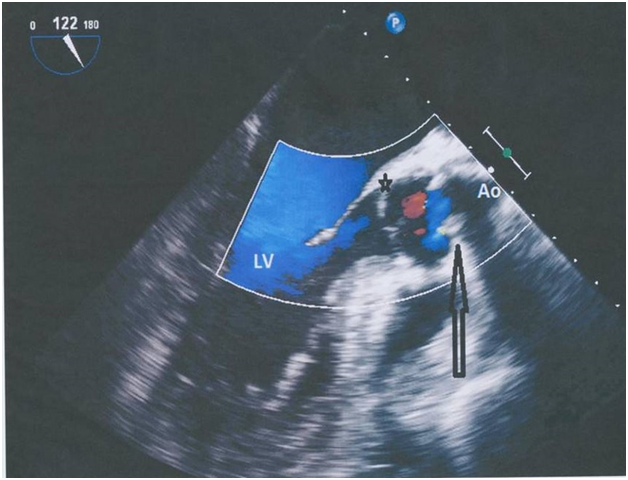

A 59year old, obese, hypertensive, male was admitted for emergent surgical repair of an acute type A, aortic dissection. He was taken to the operating room where a straight tube graft (size 28mm in diameter) was used to replace the dissected part of the ascending aorta from the sinotubular junction to the underside of the arch (hemi-arch replacement) with moderate hypothermia and antegrade cerebral perfusion. The patient separated from cardiopulmonary bypass with difficulty, moderate doses of inotropes and high filling pressures which normalized few hours postoperatively. He was extubated 36hours later, only to be re-intubated few hours later in the midst of pulmonary congestion, high filling pressures, fever and laboratory signs of hemolysis. Transthoracic echocardiography revealed a severe supravalvular aortic stenosis with an estimated systolic gradient of 110mmHg and peak velocity of 4.8m/s (Figure 1).

Figure 1 Transthoracic Echocariogram: Supra-valvular stenosis (arrow).